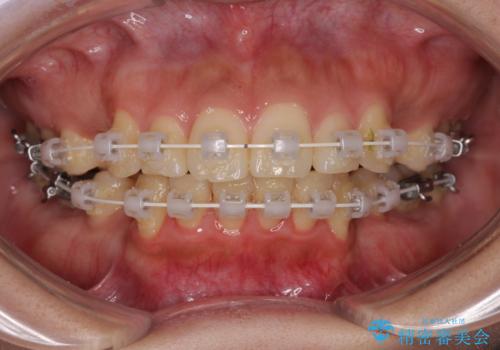

- 審美装置

- 1年7ヶ月

- 前歯のデコボコと口元の突出感を気にして来院された患者様です。

上下前歯がくちばしのように突出していたため、上下左右の第一小臼歯4本を抜歯し、ワイヤー装置にて矯正治療を行うこととしました。